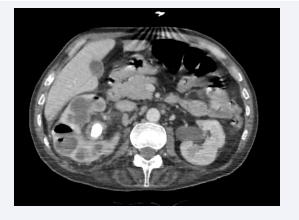

Axial section of an abdominal CT scan without intravenous  contrast injection showing air bubbles in the parenchyma and  excretory tracts of the right kidney and in the excretory and perirenal  tracts of the left kidney. The appearance is compatible with bilateral  EPN, class 4 according to Huang et al.

Figure 2: Axial section of an abdominal CT scan without intravenous contrast injection showing air bubbles in the parenchyma and excretory tracts of the right kidney and in the excretory and perirenal tracts of the left kidney. The appearance is compatible with bilateral EPN, class 4 according to Huang et al.